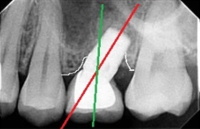

Replacement of failing lower back teeth

Immediate implant molar replacement involves placing a dental implant directly after tooth extraction in a single, minimally invasive procedure. This technique reduces healing time and preserves jawbone structure. It’s ideal for patients seeking swift treatment without extensive surgical intervention, enhancing overall dental care efficiency.

CAD/CAM dentistry uses digital technology for precise, efficient design and manufacturing of dental restorations, offering quicker turnaround and enhanced accuracy compared to conventional methods, which rely on manual impressions and techniques.